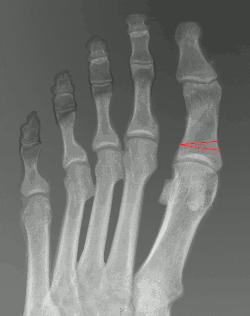

The surgery is often performed under local anaesthesia. Through a small incision made on the medial side of the big toe, a wedge-shaped piece of the bone is removed from the proximal phalynx. The toe is then realigned to its correct position and secured using pins, screws or a plate.